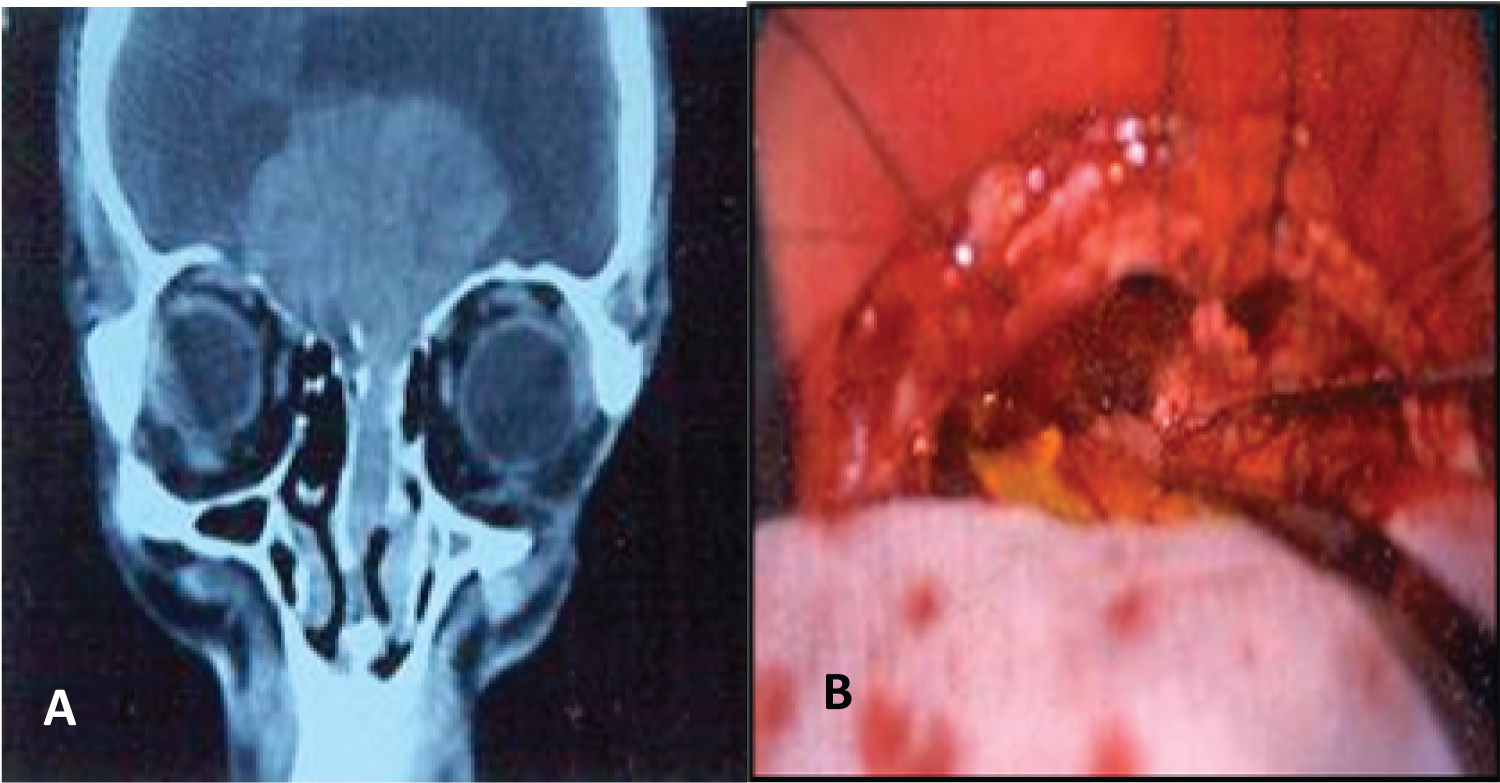

The surgical techniques used varied according to time, before the year 2000 the surgeries were performed using an external approach (Figure 1) or a combination of an external and endonasal approach (cranionasal with endoscopes in conjunction with the neurosurgeon) (Figure 2).

Figure 2: Schwannoma with endocranial involvement and bilateral decrease in visual acuity (A) Coronal CT; B) Endoscope-assisted cranionasal resection: View from the craniotomy. View Figure 2

The resection was complete in 4 patients and subtotal in another (endocranial extension with bilateral compromise of vision due to compromise of the chiasm and the proximal sector of the optic nerves).

In four patients during the mean follow-up time (2 years) no recurrences were detected. The patient with schwannoma who had intracranial extension improved vision and nasal obstruction, and residual tumor growth was not detected during the controls (Table 1).

The treatment of these tumors is surgical, with the intention of performing a complete resection. Its growth is slow, therefore subtotal resection may be indicated in tumors adhered to neurovascular structures, as in the case of the patient described in our study who had intracranial and vision compromise.